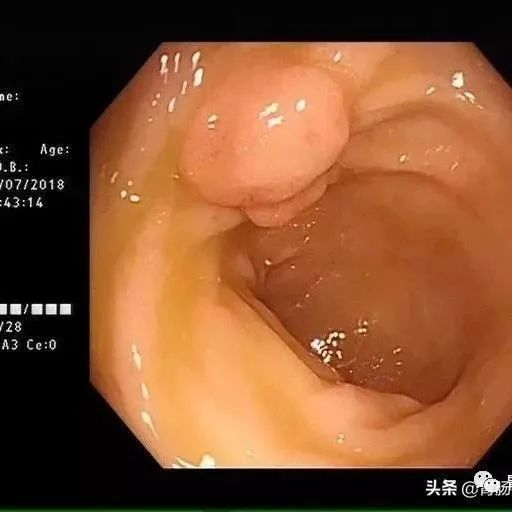

仅供医学专业人士阅读参考90后是如何虐胃的?早预防、早检查、早治疗什么是肠息肉?肠息肉就是肠道黏膜上所有隆起性的病变的总称,从结肠黏膜表面突出到肠腔的息肉状病变,通俗地说,就是肠道上长了一些肉疙瘩,人体的整个消化道都可以有息肉生长,其中以结肠和直肠息肉为最多,小肠息肉比较少。在未确定病理性质前均称为结肠息肉。息肉的病理学类型包括了肿瘤性和非肿瘤性病变。炎症性息肉、增生性息肉、错构瘤性息肉等,一般不会癌变,称为非肿瘤性;...

我们做肠镜检查,最常见的赘生物就是息肉,其中的腺瘤性息肉,其实就是肠癌的预备状态,90%以上的结直肠癌是它演变而来的。而腺瘤性息肉在50岁之后的检出率非常高。一项研究显示:在7203例次肠镜检查中,息肉检出率为:50岁前为17%,50~59岁为35%,60~69岁为56%,>70岁为63%。以上数据还不包括结肠息肉病、P-J综合征、进展期结肠癌、肠道准备不合格者及检查失败者。研究显示,直径超过2cm的腺瘤恶变率高达50%,多发性家族性息肉病癌变率可达100%,且发生癌变的年龄较轻。...

一文读懂肠息肉—— 为啥会长肠息肉?严重吗?如何治疗?怎样预防?【附手术视频】

本文作者:杨炳灿,华西厦门医院消化疾病中心本文原创:阿炳消化时间,欢迎关注01什么是肠息肉肠息肉是指从肠道黏膜表面突出到肠腔的隆起性病变,在未确定病理性质前均称做肠息肉。其发病率随年龄增加而上升,男性多见。根据病理可分为腺瘤性息肉和非腺瘤性息肉。腺瘤性息肉主要包括管状腺瘤、绒毛状腺瘤、管状绒毛状腺瘤,非腺瘤性息肉主要有增生性息肉、炎性息肉、错构瘤性息肉等。02息肉是否会癌变在所有肠癌中,80%~95%以上的肠癌都是由腺瘤性息肉慢慢演变发展而来的...